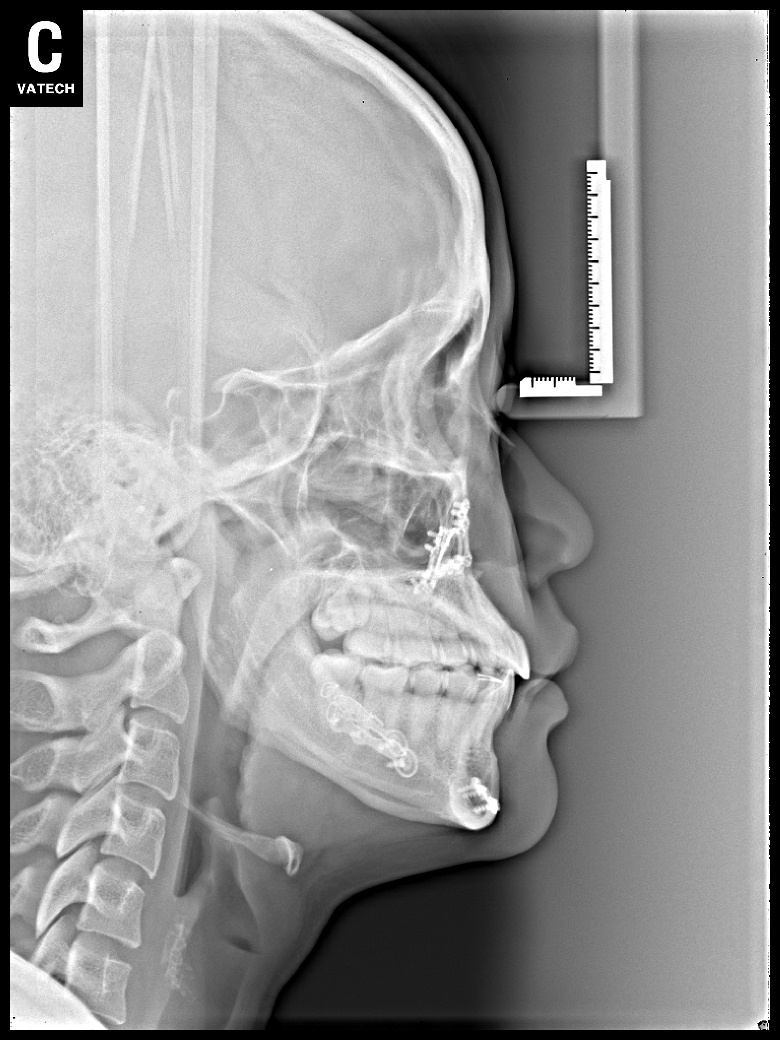

치료 후 사진입니다.